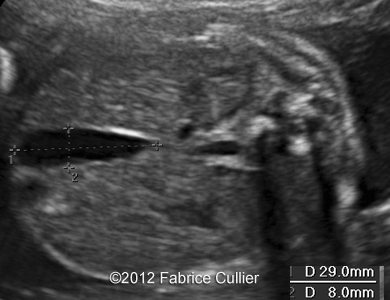

At 20 weeks, the sonographer found out a unilateral right cleft lip without other associated anomalies (Image 1-4).

Image 1-4: